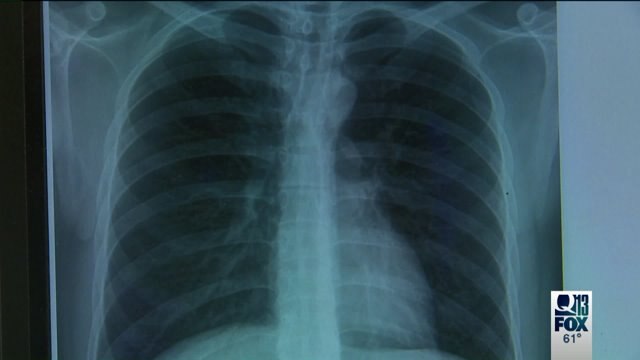

Sarcoidosis Awareness Month